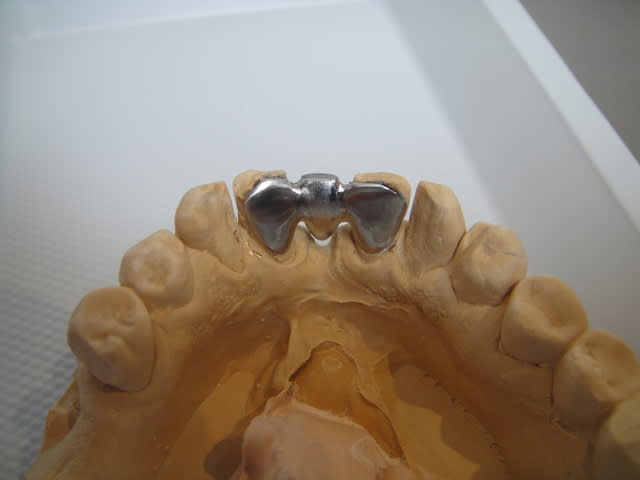

je vais faire un bridge collé avec pins dentinaires et fraisage amelaire (armature métal scellée)

la suite pour blette que ça interesse .je suis agréablement surpris de la de la rétention et de la stabilité données par cs 2 pins dentinaires

photos lundi ou mardi scellé

Brideg coll  001 mbookn - Eugenol

Brideg coll  002 cztmdu - Eugenol

Brideg coll  003 jqzbus - Eugenol

Brideg coll  004 kfuszo - Eugenol